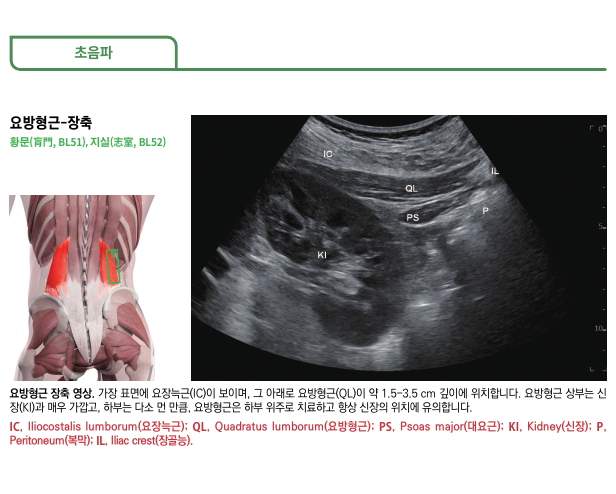

안녕하세요​대한한의영상학회 교육이사안태석 원장입니다​​저는 12년간 경혈 초음파를 활용하며정확하고 효과적으로도침과 약침을 시술하는임상 초음파 연구자입니다.​​​오늘 소개해드릴 치료 케이스는​허리 디스크 치료할 때한번쯤 확인해봐야 할 내용입니다​​디스크가 아닌<다른 질환>은 아닌지​딱 3분만 집중해서 읽어보시길 바랍니다. ​​​ 허리 디스크 탈출증 환자,이번